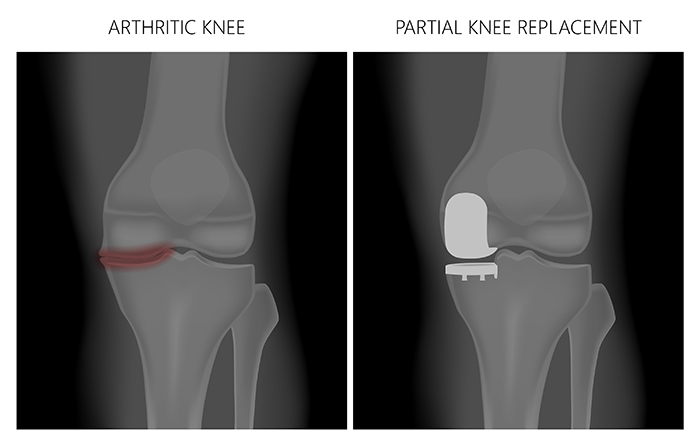

Unicompartmental knee replacement is a minimally invasive surgery in which only the damaged compartment of the knee is replaced with an implant. It is also called a partial knee replacement. The knee can be divided into three compartments: patellofemoral, the compartment in front of the knee between the knee cap and thigh bone, medial compartment, on the inside portion of the knee, and lateral compartment which is the area on the outside portion of the knee joint.

Traditionally, total knee replacement was commonly indicated for severe osteoarthritis of the knee. In total knee replacement all worn out or damaged surfaces of the knee joint are removed and replaced with new artificial parts. Partial knee replacement is a surgical option if your arthritis is confined to a single compartment of your knee.

Osteoarthritis is the most common form of knee arthritis in which the joint cartilage gradually wears away. It most often affects older people. In a normal joint, articular cartilage allows for smooth movement within the joint, whereas in an arthritic knee the cartilage itself becomes thinner or completely absent. In addition, the bones become thicker around the edges of the joint and may form bony “spurs”. All of these factors can cause pain and restricted range of motion in the joint.

Unicompartmental knee replacement, also called a partial knee replacement is surgery to treat arthritis which is limited to one of the knee compartments. During the surgery, only the damaged compartment of the knee is removed and replaced with metal and plastic, leaving the remaining healthy cartilage and bone.